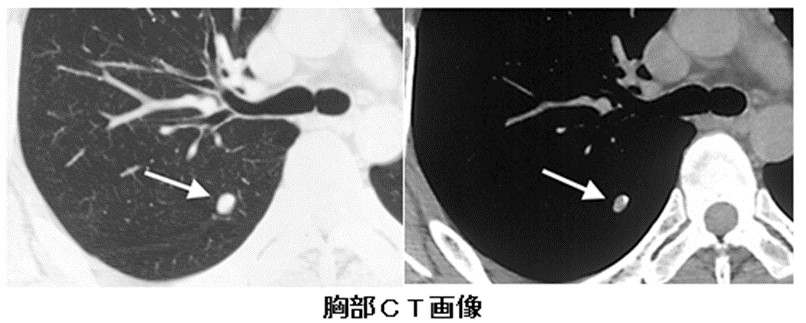

胸部のCT 胸部CT検査 | 呼吸器の検査 | 各検査を知る | 人間ドック | 健診の詳細情報

胸部CT検査 | 呼吸器の検査 | 各検査を知る | 人間ドック | 健診。CT装置のご紹介 | こうのす共生病院|埼玉県鴻巣市。胸部CT | 画像診断検査 | 各検査を知る | 人間ドック | 健診会。医師解説】胸部CT検査の基本とCT写真の見方完全ガイド(※言い。「胸部のCT」村田 喜代史 / 上甲 剛 / 村山 貞之定価: ¥ 15000#村田喜代史 #村田_喜代史 #上甲剛 #上甲_剛 #村山貞之 #村山_貞之 #本 #自然/医療・薬学・健康裁断済み中身は未使用に近い